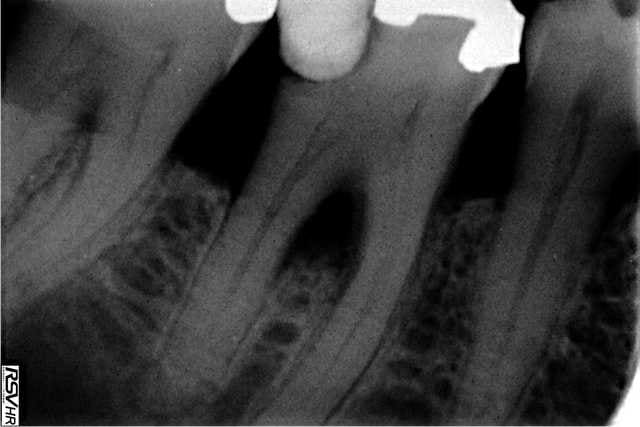

tiens une photo prise 20 secondes après une péri-apicale sur une 27....là où on pique toujours, zone facile... douleur fulgurante et vasoconstriction massive de la joue gauche...

C'est de la merde la péri apicale...

Ca me fait plaisir cette photo j'ai la même dans le tiroir.

Ca m'est arrivé sur la même patiente 2 fois une sur la 17 et une sur la 27. ;-)

Quelle est la CAT dans ce cas?

Injection intravasculaire?

Tu aspires pour contrôler avant de pousser sur le piston?